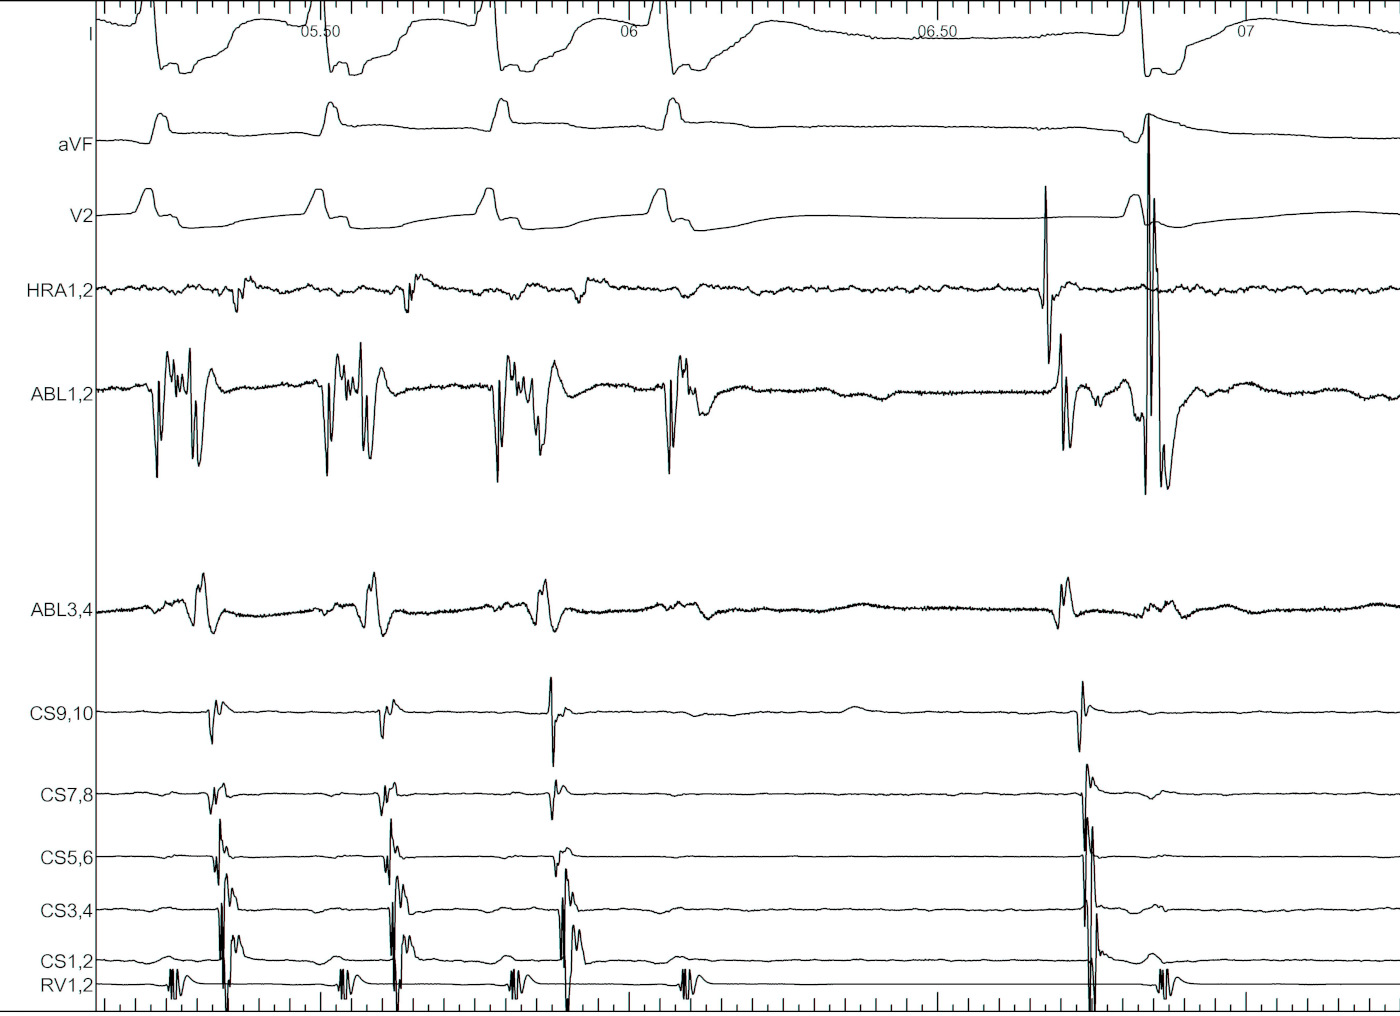

signals.jpg

Mapping in diverticulum - CSE potential most important